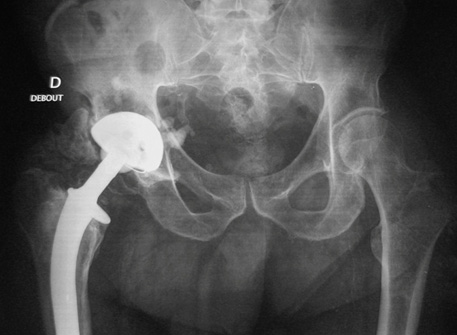

Mr F., 72 ans, a été opéré d’une prothèse totale de hanche droite.

Tout s’est parfaitement bien passé. Les mobilités per et post opératoires étaient satisfaisantes sans douleur.

Durant la semaine d’hospitalisation, la mobilité de la hanche droite a diminué sans douleur, et 45 jours après les amplitudes articulaires de la hanche opérée étaient très réduites : une vingtaine de degrés de flexion, aucune rotation.

Une nouvelle radiographie est demandée et retrouve une ossification périprothétique importante.